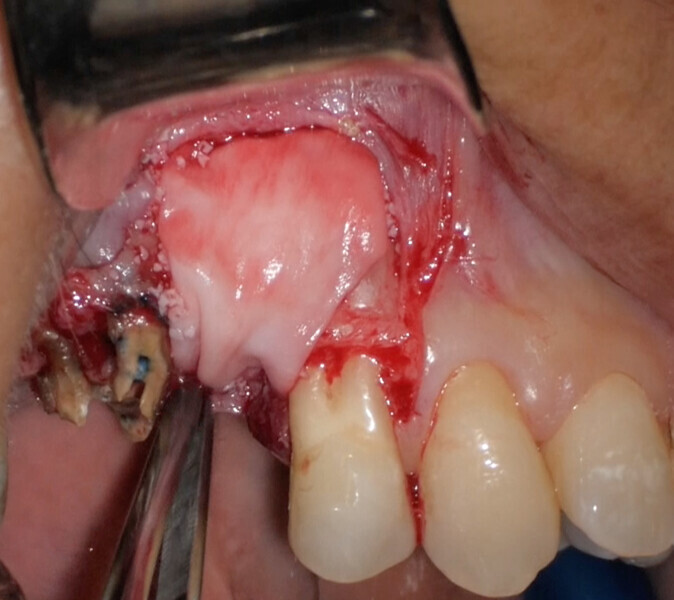

Use of 3D technology in the diagnosis and treatment of endodontic disease